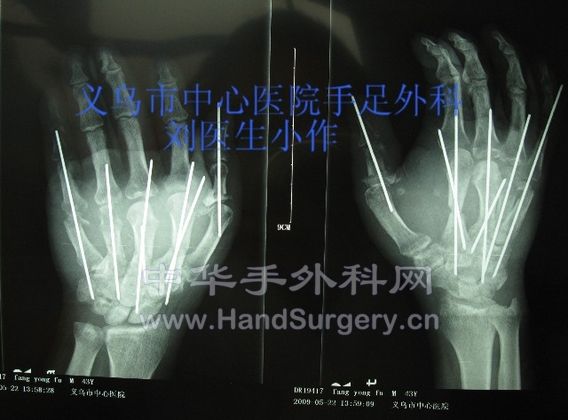

这是一例是高处电梯坠落所致严重压砸性加撕脱性断掌再植,术中处理较复杂,还望各位高手指点。目前术后有一定活动功能。

撕脱性断掌再植 (3).JPG

撕脱性断掌再植 (4).JPG

手术中拇指静脉动脉都做了移植。屈肌腱远端都选择缝合深屈肌腱为主。浅屈肌腱未作缝合。谢谢 4# suewen120

请问楼主骨折是用什么方法处理的 有没术前、后X片.....期待